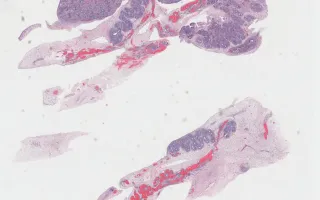

Ovotestis, Simpson-Golabi-Behmel Syndrome, H&E stain

This fetus also had gonads with an indeterminate appearance on gross examination, corresponding histologically to gonads with both ovarian and testicular differentiation (“ovotestes”).

The overall findings in this fetus included increased growth parameters, congenital diaphragmatic hernia, nephroblastomatosis, and ovotestes.

This slide shows H&E stain. See Related Content section for other stains, specimen photograph and kidney slides: